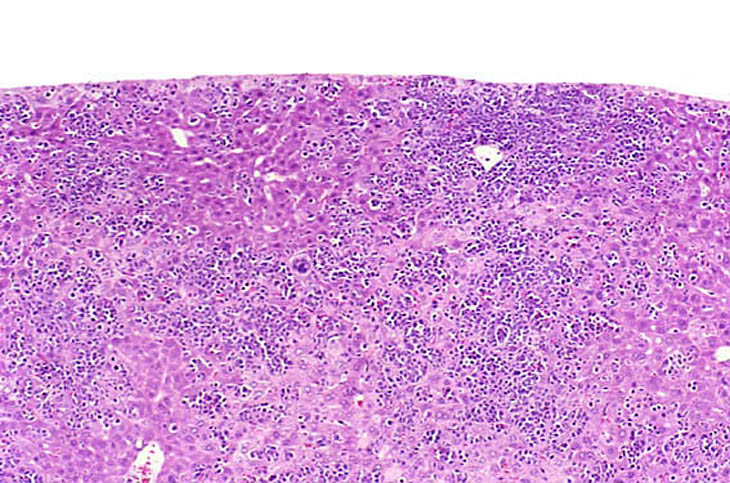

The liver is a relatively frequent site of infiltration by malignant lymphocytes, especially in strains with a high prevalence of lymphoma.

Infiltration of malignant lymphocytes in a liver from an adult mouse.

Severe infiltration of the liver by malignant lymphocytes. Hepatocytes visible in the lower right corner.